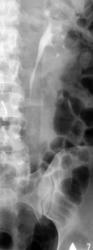

Иллюстрации 1, 2. На обзорной рентгенограмме области почек и мочевыводящих путей слева на уровне Т12 и Л1 определяются две тени характера конкрементов различных размеров значительной интенсивности неоднородной структуры.

Иллюстрации 6, 7. После введения контрастного вещества функция с обеих сторон. Слева почка обычного расположения, формы и размеров. Вышеописанные конкременты располагаются в эктазированных малых чашечках. Мочеточник обычного калибра, прослеживается на всем протяжении.

Иллюстрации 8, 9. Четко дифференцируются конкременты в малых чашечках левой почки. Справа определяется контрастирование малых чашечек в виде нечётко очерченных «лужиц».